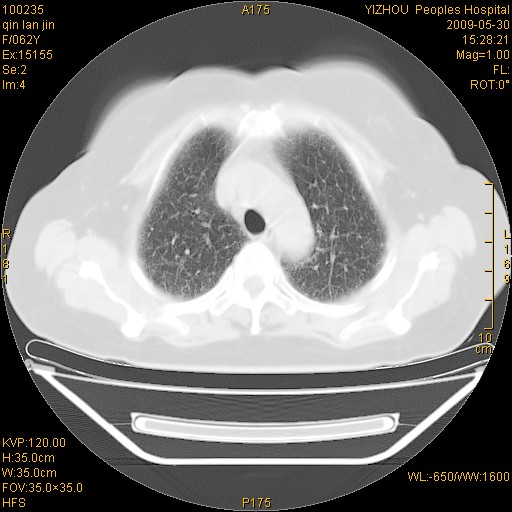

标题: CT20268:肺泡癌?间质性肺炎? [打印本页]

标题: CT20268:肺泡癌?间质性肺炎?

女,62岁,近二年经常咳嗽,近二个月,消瘦、乏力。

弥漫性双肺间质纤维化。

两肺弥漫性间质性病变(间质性肺炎伴肺间质纤维化?)。

弥漫性双肺间质纤维化

间质性肺炎伴肺间质纤维化。